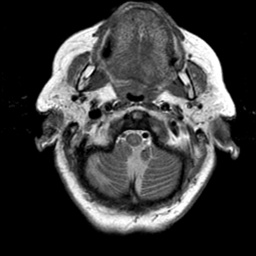

To demonstrate the effectiveness and efficiency of the proposed image fusion method , we conduct a set of comparative experiments on three image datasets. The first is composed by 8 pairs of multi-modal medical images and the second one contains 15 pairs of multi-focus gray or color natural images. These two datasets are often used in many related papers and some examples are shown in Figure 3(a) and Figure 3(b). The third one is a new multi-focus cervical cell image dataset collected by ourselves, which consists of 15 groups of color images and each group contains a series of multi-focus cervix cell images with size of or , etc. Some source examples are shown in Figure 3(c). Our source code implemented in C++ along with the new multi-focus cervical cell image dataset is available online.

We first evaluate the performance of the proposed method under varying total number of octaves and number of layers sampled per octave. The fused images of a pair of multi-modal medical images with different and are shown in Figure 4. In this example, on the one hand, when only 1 or 2 octaves are involved in constructing the DoG pyramid, the fused images fail to keep the integrity information of large size objects (e.g. eyeballs), while by increasing the value of , the integrity information of eyeballs is preserved. On the other hand, although not as significant as the increase of octave numbers , the fused image can contain more details by the increase of layer numbers . The corresponding objective quality metrics are shown in Figure 5. As shown in Figure 5(a), most of the metric values are improved as the number of octaves increases with the fixed layer numbers 3 in the global tendency and each of them tends to be stable when the number of octaves is 5. To get a relatively good quality from Figure 5(b), we can notice that some of the metric values can get a good performance when the number of layers is 3, such as the MI, SSIM, QI and VIF, though there are only a little change of all the metric values by increasing the number of layers with the fixed octave numbers 5. Because it will result in more computation burden with the increase of the value and , and for different kinds of source images, there are different performance with the diverse parameter settings. To get a trade-off between them in our experiments, we set for the multi-modal dataset, for the natural datasets and for the multi-focus cell dataset, respectively.

Figure 6 shows the fused images obtained by different methods with the multi-modal source images shown in Figure 3(a). As shown in these figures, the proposed method can produce images which preserve the complementary information of different source images well. Moreover, due to the scale-invariant structure saliency selection, our method can keep the integrity information of large size objects and the visual details simultaneously. Although the fused image generated by other methods can also capture the details to some extent, all of them fail to keep the integrity information of large size objects such as the eyeballs. Furthermore, from Figure 6(k)-6(t), the DTCWT, GFF, IM and NSCT methods may decrease the brightness and contrast while the proposed method can preserve these features and details without producing visible artifacts and brightness distortions.